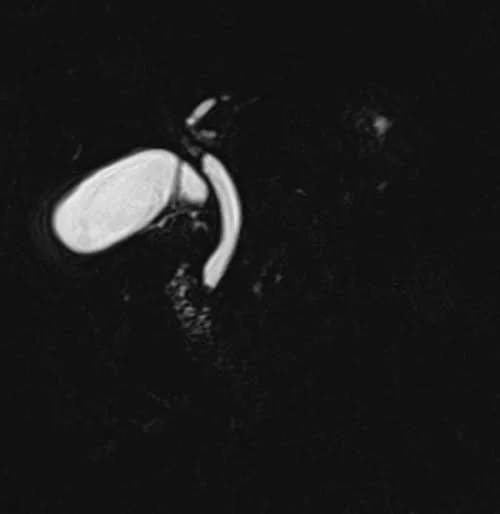

- MRCP: SPACE sequences, especially heavily T2-weighted variants, are ideal for MR Cholangiopancreatography (MRCP) studies. They can clearly delineate the biliary tree and pancreatic ducts without the need for contrast, providing a non-invasive alternative to procedures like ERCP.

- Very useful for 3D MRCP imaging (respiratory gated SPACE scans)

T2 SPACE fat sat coronal sequence used in MRCP imaging